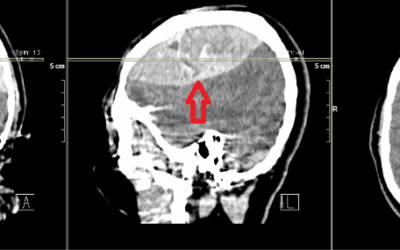

Beyin Tümörü

Beyin Tümörü Nedir? Beyin tümörü, beyindeki hücrelerin kontrolsüz şekilde büyümesi sonucu oluşan anormal bir kitle veya büyümedir. Bu tümörler iyi huylu (benign) veya kötü huylu (malign) olabilir. Beyin tümörleri, doğrudan beyinden kaynaklanabilir (birincil...